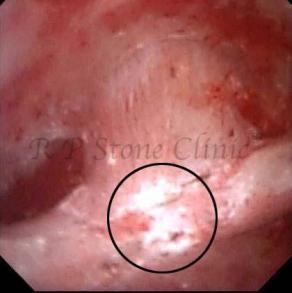

These images are taken as snap shots from the video recording of RIRS Surgery done at our hospital. These are Randall’s Plaques seen with Digital FLEX XC & Digital FLEX XC S. The cream or whitish patches are seen on the tips of RENAL PAPILLAE as seen in images below.

Randall’s Plaques may lead to the formation of Stones.

Those kidney stone patients who have Randall’s Plaques in their kidneys are more likely to form stones again (Recurrent Stones).

Stone Patients in whom Randall’s Plaques are detected at the time of RIRS Surgery should undergo regular ultrasound examination for early detection of stones.

Patients of Stones with Randall’s Plaques in their Kidneys should drink plenty of fluids in addition to Orange Juice & Lemonade.